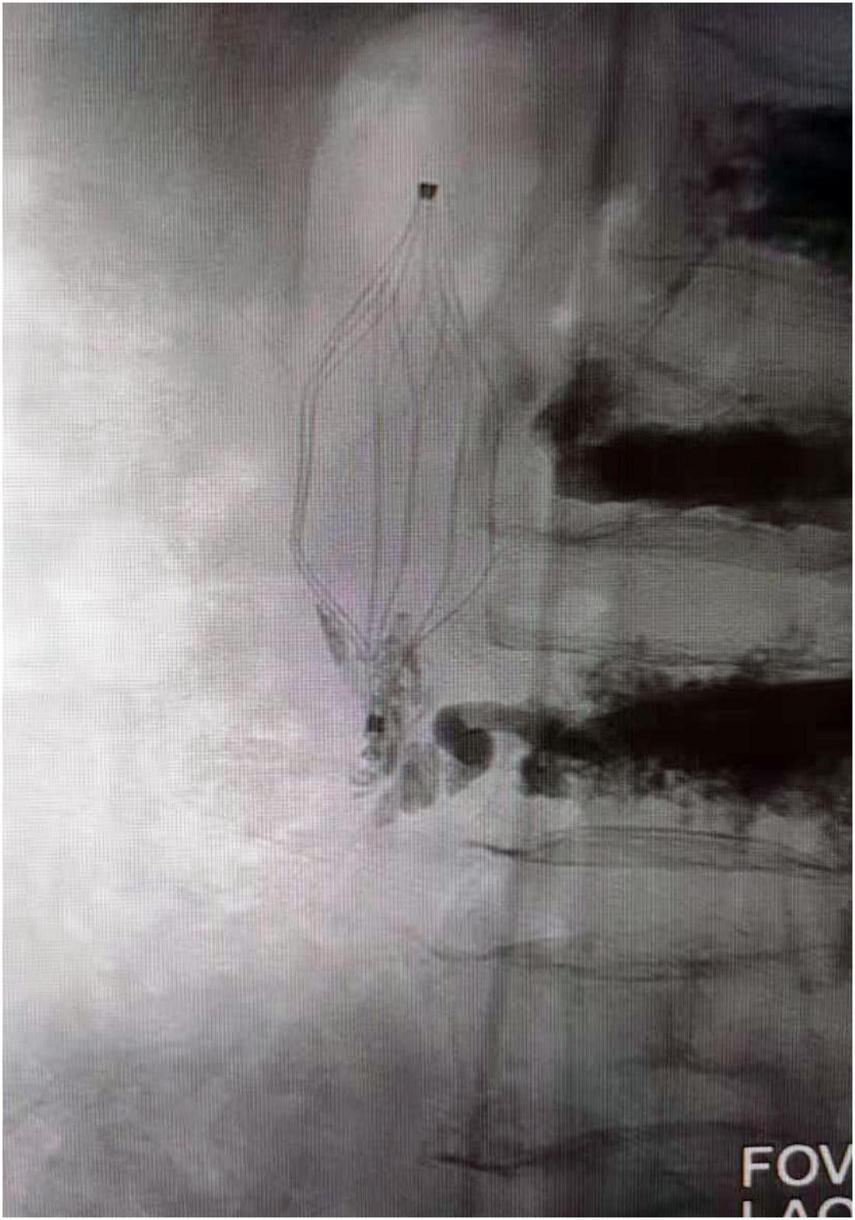

Thereafter, X-ray examination showed paravertebral venous cement leak and cement entry into the IVC, resulting in the deposition of a cement cast in the IVC filter, and CT images demonstrating cement leaking out of the vertebral body (Figure 1). An inferior vena cavography prior to retrieval of the filter showed that cement had migrated into the IVC and attached to the caval wall at the level of the IVC filter tip and was trapped within the filter (Figure 2), resulting in the IVC filter failing to be retrieved in the conventional way.

FIGURE 2

Venography showed cement attached to the IVC filter hook and trapped in the filter. IVC, inferior vena cava.